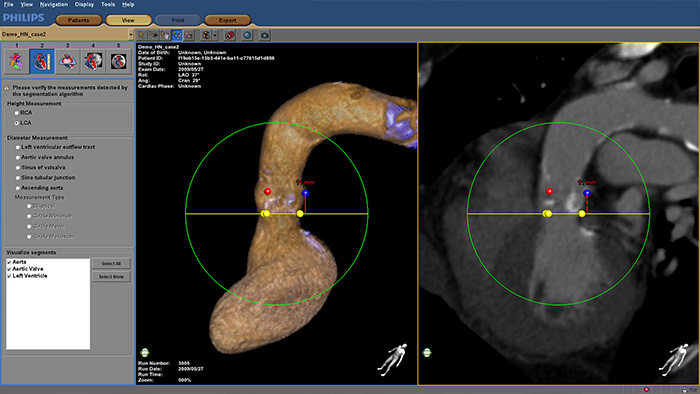

HeartNavigator procedure

HeartNavigator

Increase confidence and ease during transcatheter aortic valve replacement (TAVR) and other challenging SHD procedures. The immersive user experience is highly automated to simplify planning, device selection and projection angle selection. During procedures, it provides live image guidance to support device positioning.